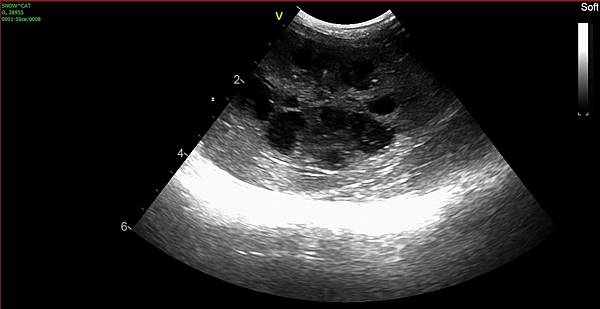

不看還好一看糟糕

膀胱裡面蠻多亮晶晶的懸浮物

可能是尿沙

自從他們倆個膀胱炎過後

每天的罐頭水不敢偷懶

但古錐就是乾乾控,罐頭水要吃不吃的

攝取的水量沒有墨墨那麼好